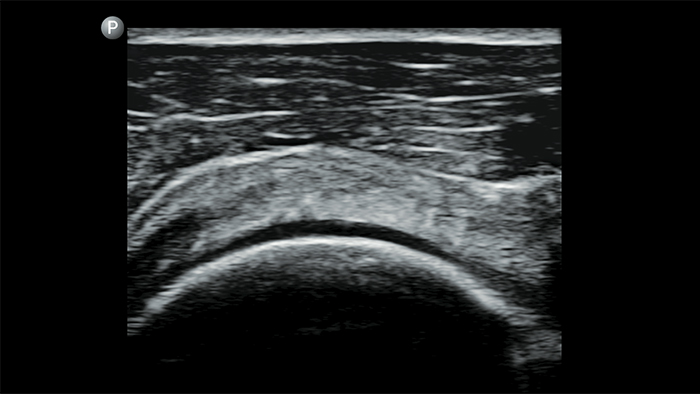

Exceptional ultrasound imaging

Lumify handheld ultrasound offers images that enhance diagnostic confidence.

See more when it counts

Lumify can help you make real-time decisions with more confidence, from assessment to recovery. Reveal the subtle details of an image, uncover enriched tissue definition with multiple angles and much more.